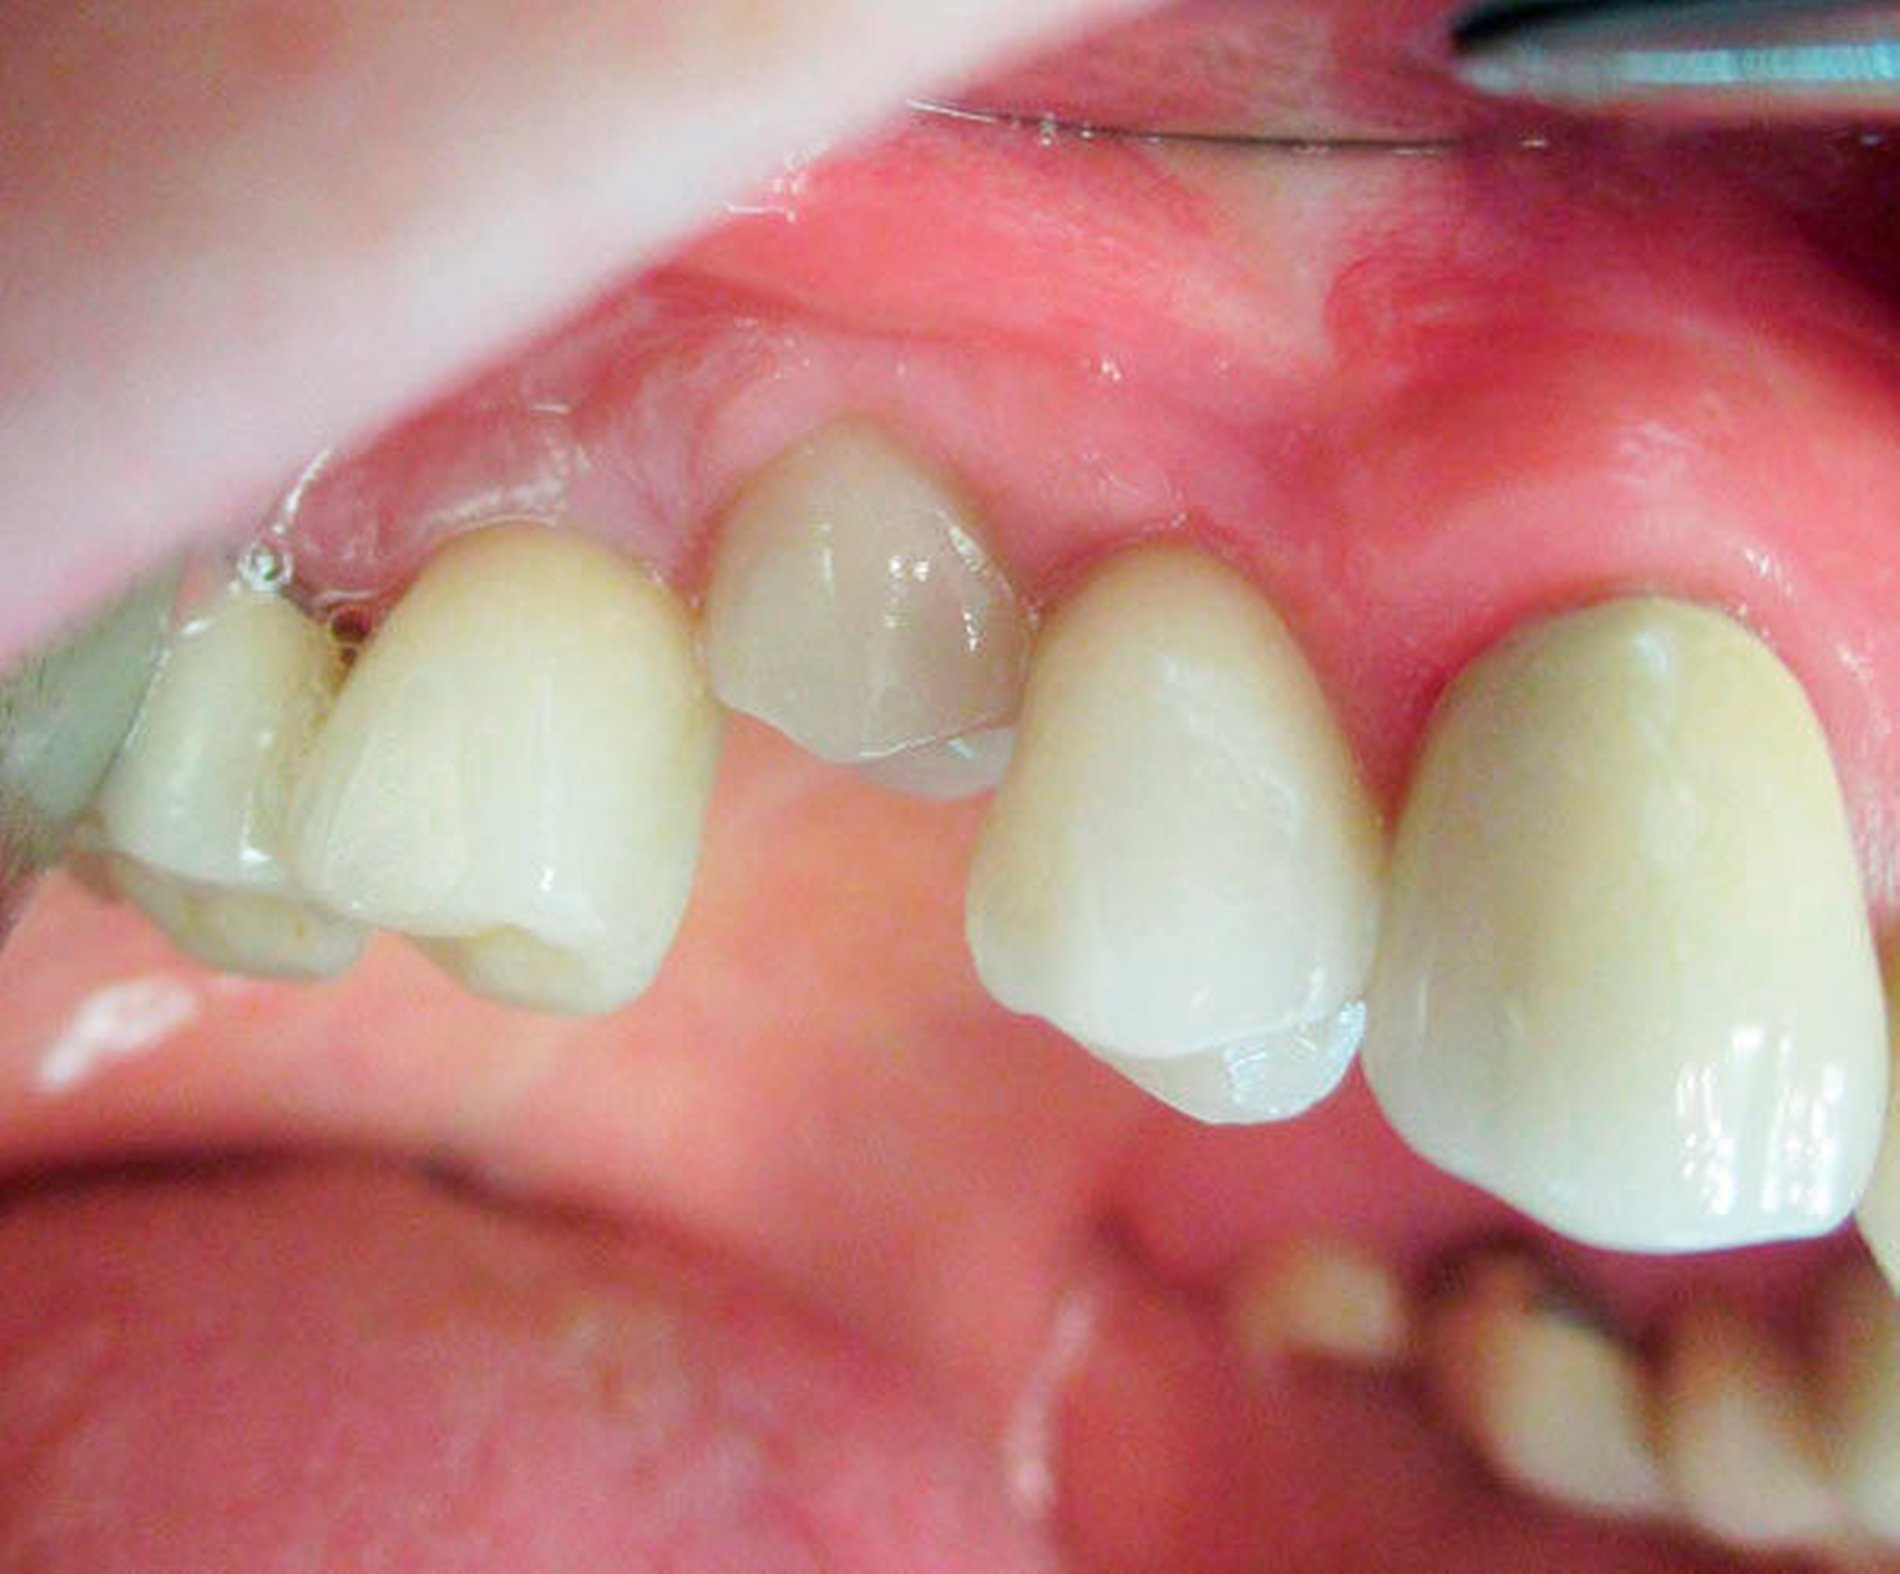

Nach Freilegung und prothetischer Versorgung im August 2015 waren die Titanimplantate und der dazwischen befindliche Zahn 15 zwei Jahre lang beschwerdefrei in situ – bis Ende April 2017 der Zahn 15 beim Kauen eines Fleischstücks spontan in die Kieferhöhle luxierte (Abbildungen 1 und 2).

Eine Sinusitis maxillaris bestand nicht und die Patientin litt unter keinerlei Schmerzen. Allein die unterbrochene Zahnreihe störte.